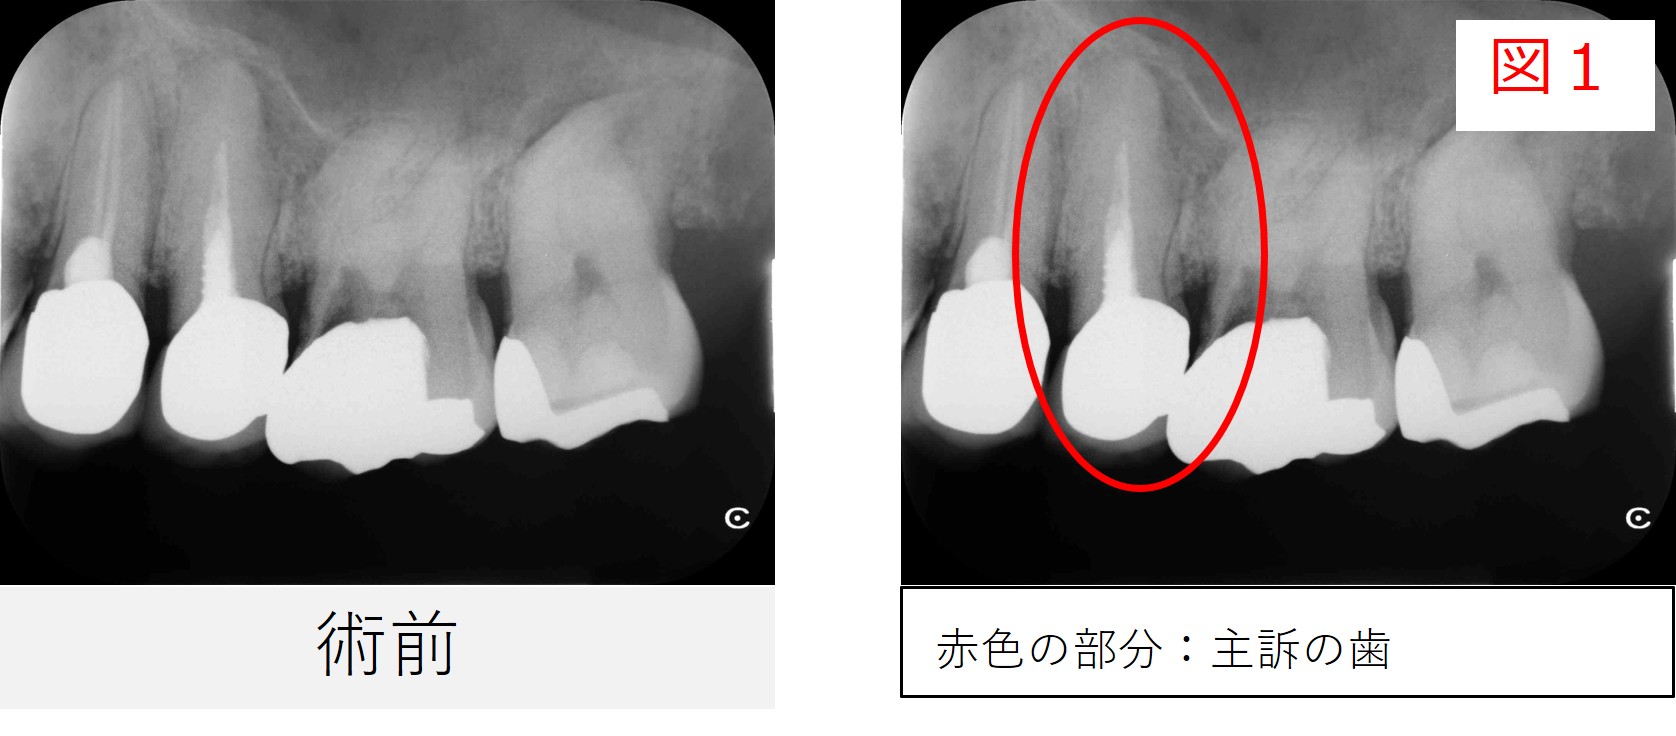

紹介時の画像診断では、左上7番だけでなく、左上5番の根の先にも黒い影が見られました。

耳鼻咽喉科での画像検査では、左上7番が主な原因と考えられていましたが、

同時に左上5番の根尖部にも透過像があるという診断でした。

●レントゲン・CT画像所見

レントゲンおよびCT画像では、左上5番の根尖部に透過像(骨のない部分)が確認されました。

このような所見は、歯の内部で感染が生じ、根の先に炎症が存在している状態で、医学的には「根尖性歯周炎(こんせんせいししゅうえん)」と呼ばれます。

また、画像所見からは、歯の内部にスクリュータイプ(ネジ型)のメタルポスト(土台)が入っていることがわかりました。